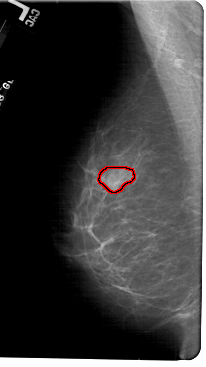

FILE: A_1833_1.LEFT_CC.OVERLAY

TOTAL_ABNORMALITIES 1

ABNORMALITY 1

LESION_TYPE MASS SHAPE LOBULATED MARGINS OBSCURED

ASSESSMENT 3

SUBTLETY 3

PATHOLOGY BENIGN

TOTAL_OUTLINES 1

BOUNDARY